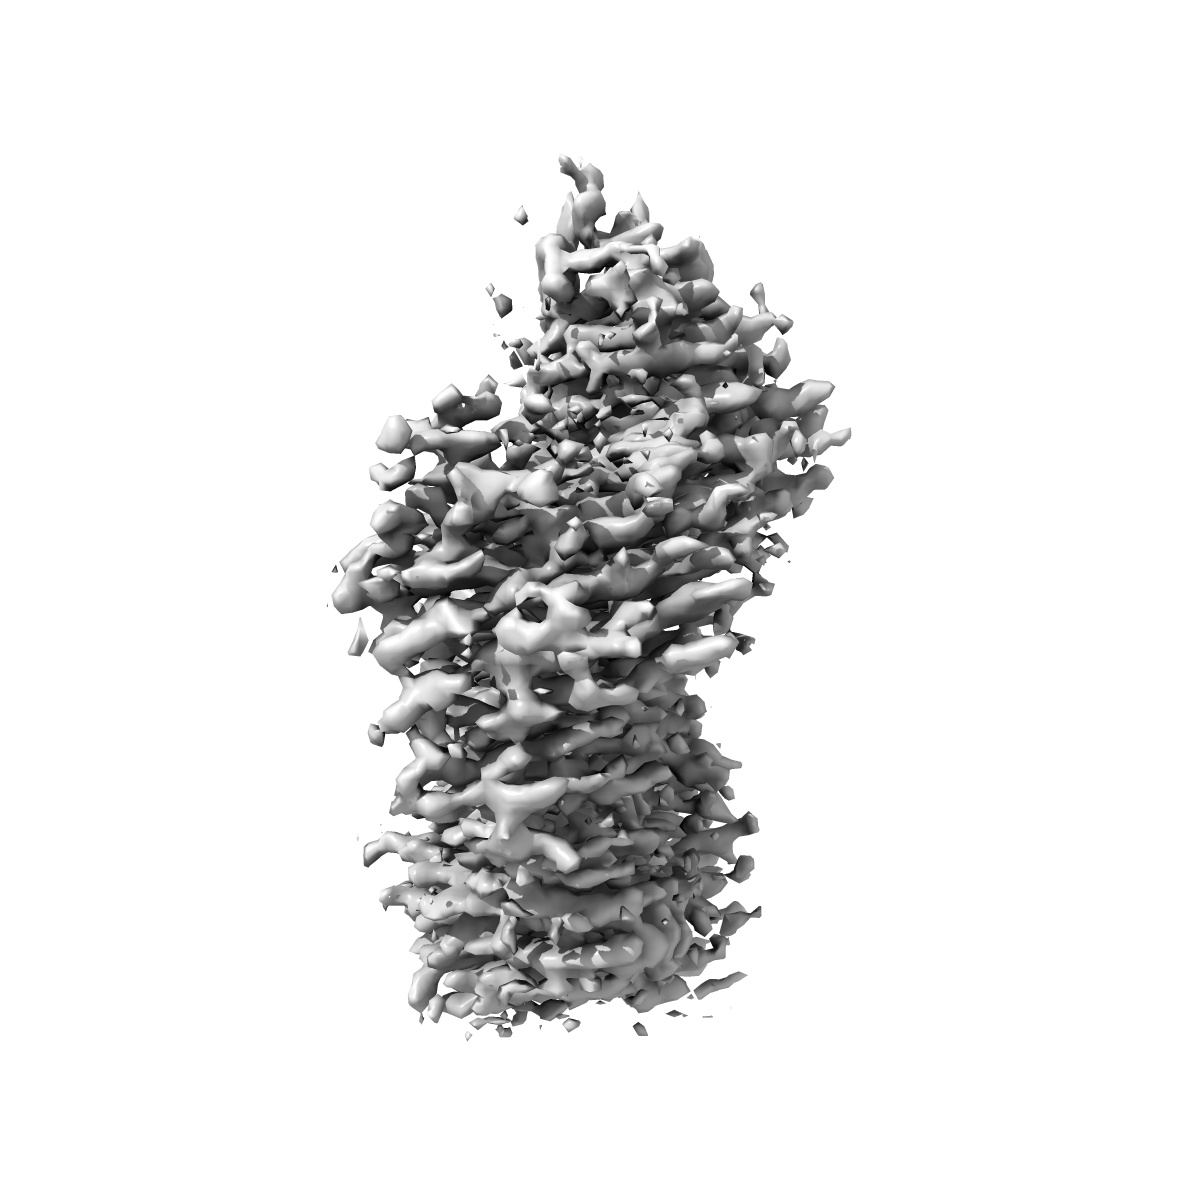

Focused refinement Fab-Nb (cryo-EM structure of inactive human arginine-vasopressin (AVP) V2 receptor (V2R) with Mambaquaretin1 K39A (MQK39A))

Sample: Inactive V2R-bril bound to tolvaptan stabillized with anti-BRIL Fab and anti-BRIL Fab Nanobody

Inactive structures of the vasopressin V2 receptor reveal distinct binding modes for Tolvaptan and Mambaquaretin toxin.

(2025) Nat Commun , 16 , 3899 - 3899